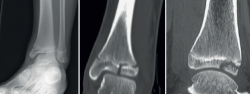

Figura 3. Imágenes radiográficas donde se ve una fractura triplanar. En la proyección lateral simula una fractura de Salter-Harris de tipo II, mientras que en la proyección coronal tiene apariencia de una fractura de tipo III o una fractura de Tillaux. Con la tomografía se puede apreciar con detalle el trazo de fractura y el desplazamiento.

En una radiografía simple anteroposterior, la fractura triplanar tiene apariencia de una fractura de S-H de tipo III o una fractura de Tillaux; sin embargo, en una visión lateral simula una de tipo II. Es por ello que muchas veces es clasificada erróneamente como una fractura de S-H de tipo IV(3) (Figura 3).